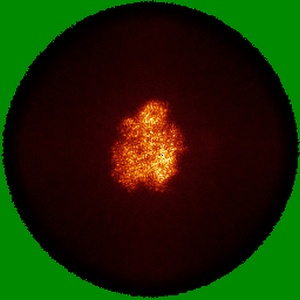

Cryo-EM structure of cancer-specific PI3Kalpha mutant E542K in complex with BYL-719

Single-particle2.77 Å

Sample: Human PI3Kalpha mutant E542K in complex with BYL-719